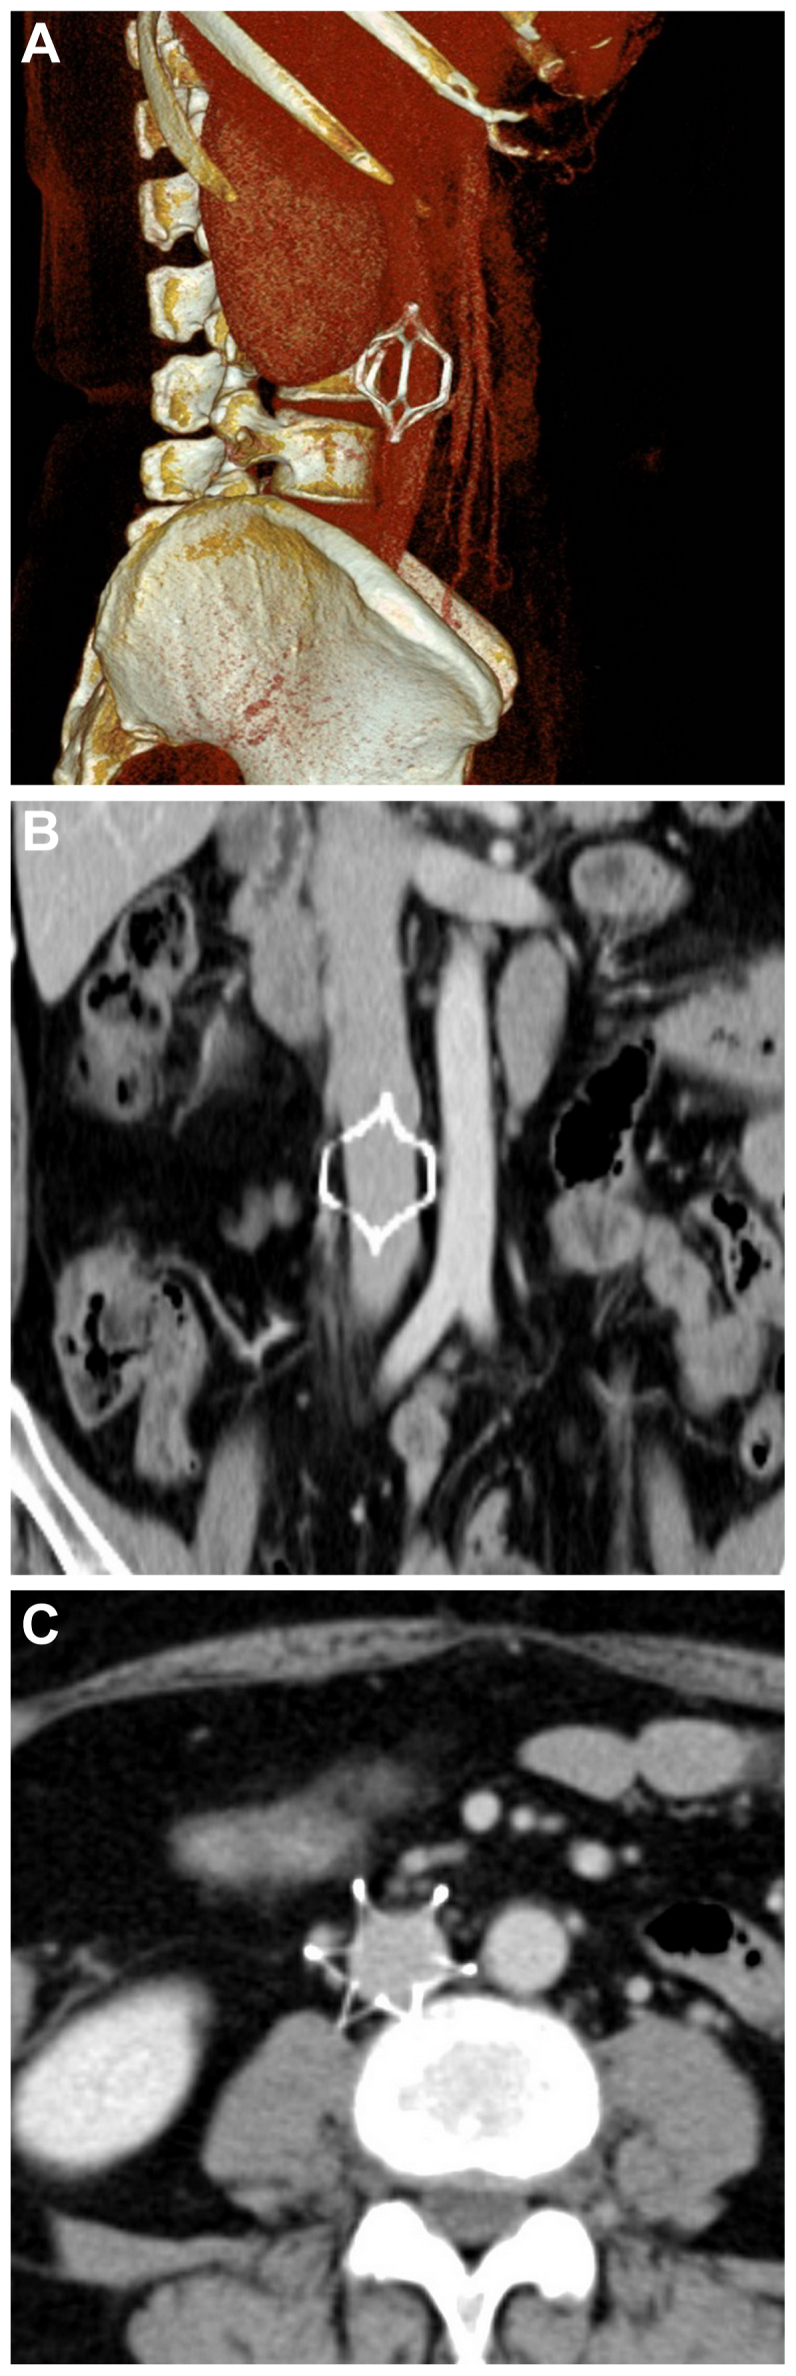

Perforation from an inferior vena cava filter with six legs

有六条腿的下腔静脉滤器穿孔。